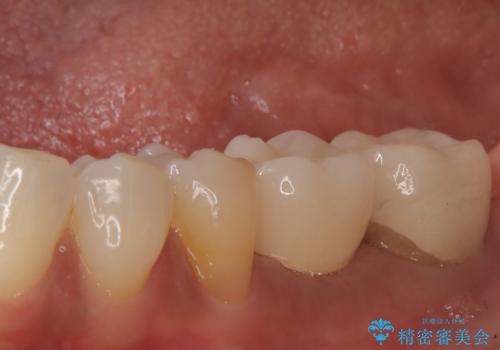

![[ インプラント体・カスタムアバットメント・ジルコニアクラウン ] インプラントの構造の症例 治療後](https://seimitsushinbi.jp/wp/wp-content/uploads/2024/02/4f5d249988cfa0d7689dd16755d46820-500x350.jpg?v=1708928265)